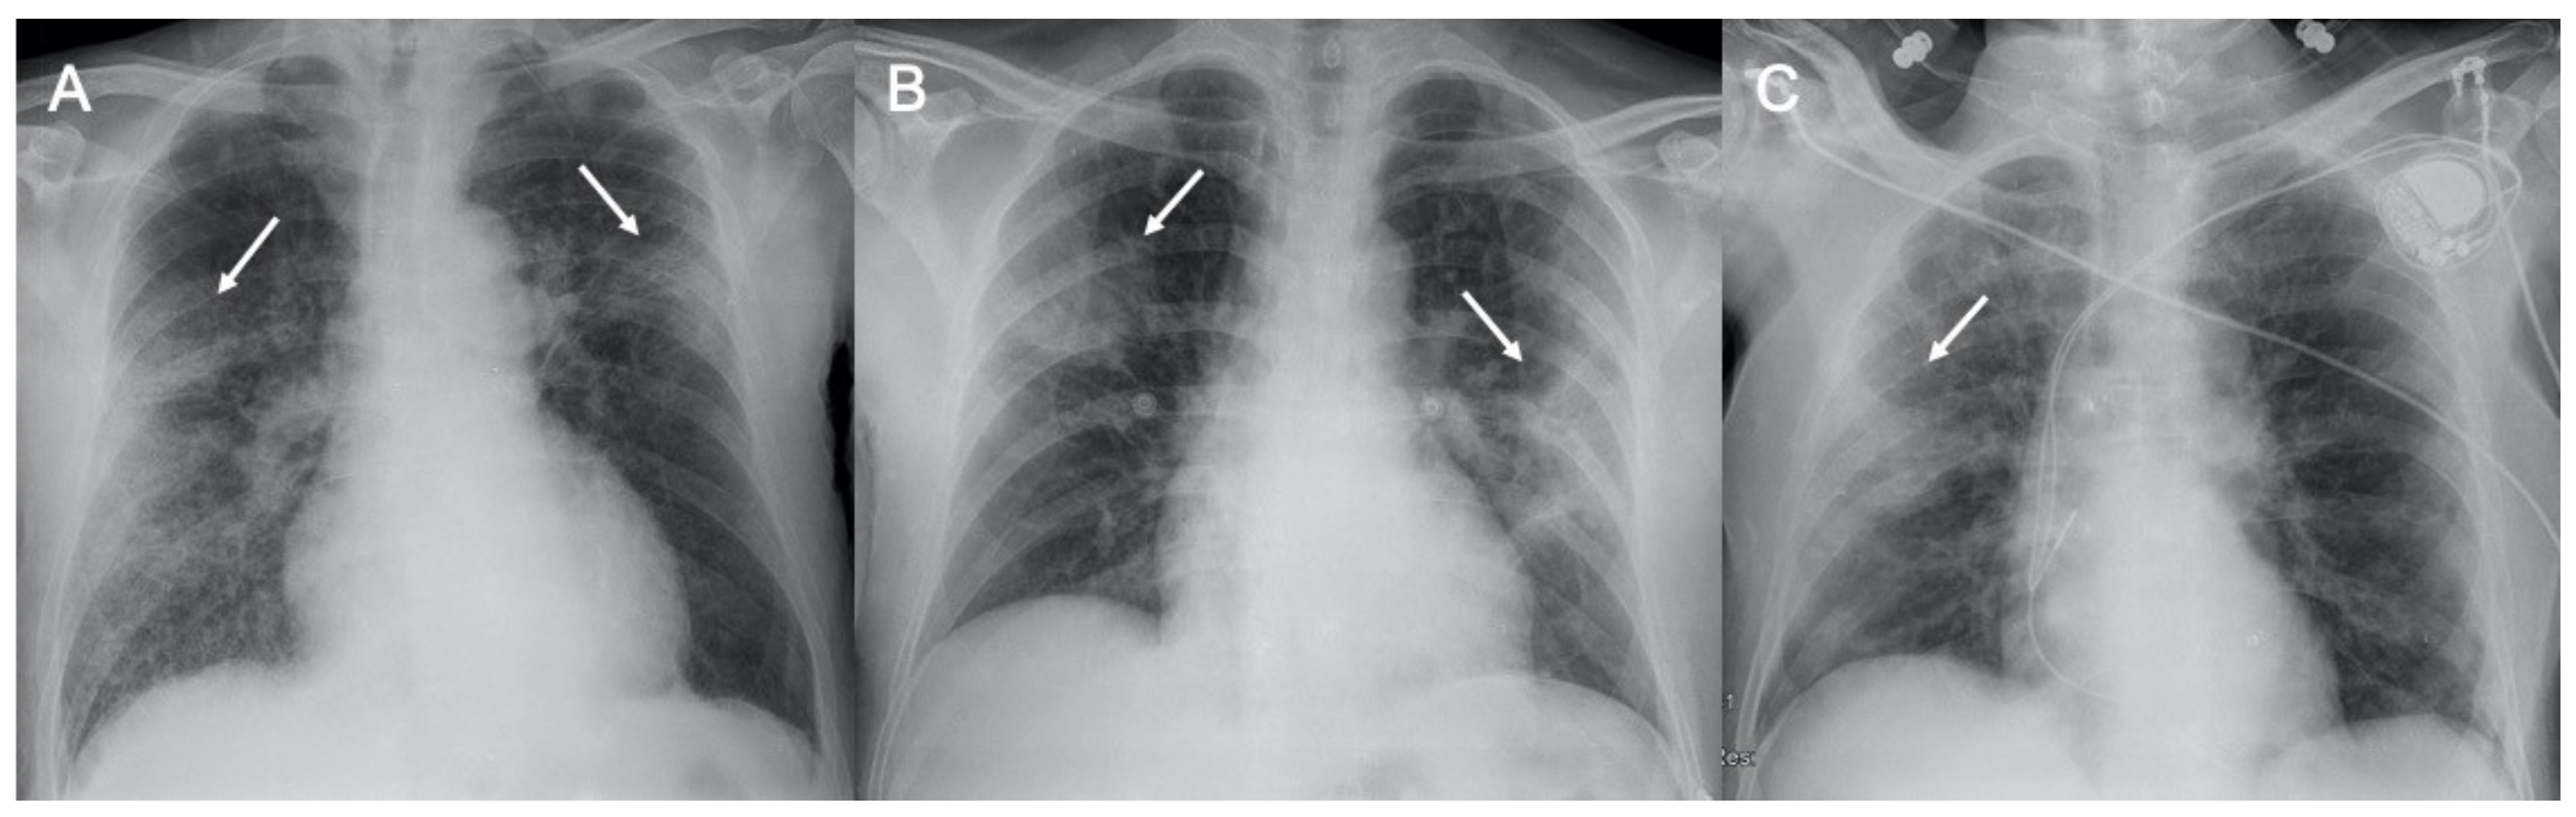

● CXR:肺胸膜下實(shí)變、磨玻璃影、結(jié)節(jié)和網(wǎng)狀結(jié)節(jié)陰影,表現(xiàn)為間質(zhì)性肺炎伴彌漫性肺泡損傷(圖1)。

圖1 新冠肺炎(COVID-19)的CXR。3例仰臥位CXR顯示胸膜下實(shí)變(箭頭),圖(A,B)顯示雙側(cè)受累,(C)主要為右肺受累